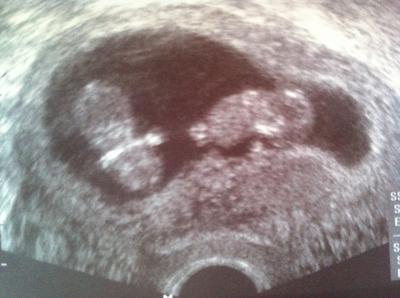

Hi Mädels, wir waren heute zum Baby Tv. Eine erste Überraschung bekam ich im Wartezimmer. Dort war mein Schulfreundin, die ich seid Jahren nicht gesehen hatte. Der Kontakt ist abgebrochen und wir schreiben und nur gelegentlich über WhatApp. Mein Mann kam mit zum Dok. Das war mir wichtig. Bei unsrem ersten Sohn kam er auch gelegentlich mit und da man ja in der 11 SSW schon etwas erkennt, kam er mit. So nun die Überraschung beim Ultraschall. Da sind 2 Babys zu sehen auf dem Bildschirm. Zwillinge... Das ist natürlich erstmal ein Schock für uns. Wir müssen das erstmal sacken lassen =)

Und tolles bild

Mega süßes Bild. Glückwunsch.